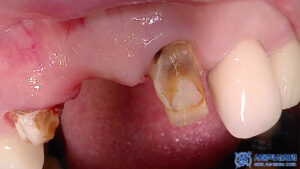

먼저 기존 브릿지를

제거하였습니다.

제거 후 확인해 보니

치아에 충치가 진행되어 있는 것을

관찰할 수 있었습니다.